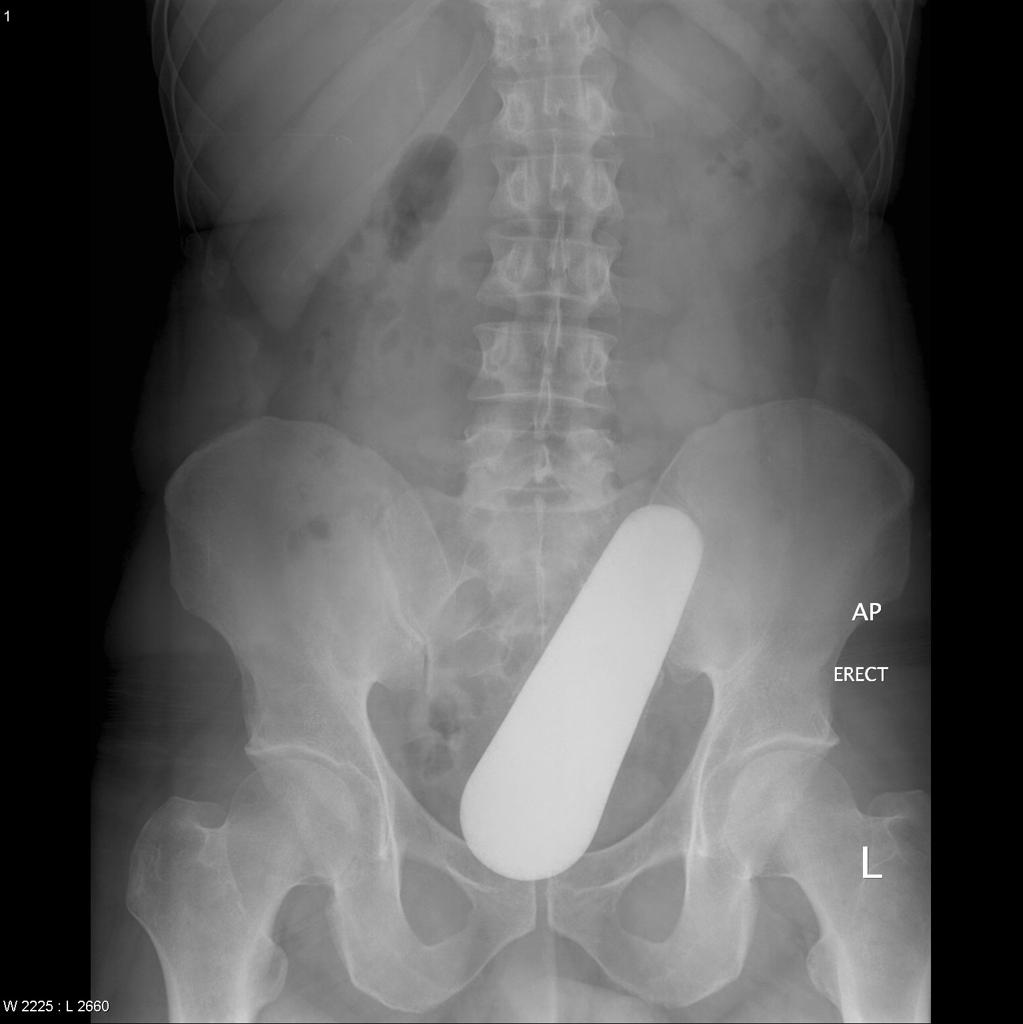

▼至於體內發現各種形狀的成人玩具,對急診室醫生來說已經見怪不怪了!

根據國外網站 Deadspin 的記載,在人體內發現的異物遠遠不止這些,當中包括:警棍、水管、牙刷、原子筆、撞球、打火機、螺絲起子、遙控器、聖誕裝飾等等匪夷所思的物品。到底在什麼樣的狀況下,才會令人將這些東西塞進自己的體內呢?如果仍然執意這樣做的話,請盡量確保自己可以取出這些物品,以免讓自己成為網路上大家的笑柄!